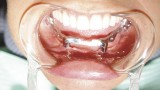

Pacjentka wyraża zgodę na zabieg chirurgiczny, polegający na wprowadzeniu wszczepów podokostnowych, zdając sobie sprawę, że jest to ostatnia deska ratunku, umożliwiająca stabilne zakotwiczenie protezy wspartej na wszczepach. Po zabiegu implantacji dwie oddzielne siatki podokostnowe (ryc. 3) zostaną ze sobą połączone (ryc. 4). Podniesiony płat śluzówkowo okostnowy (ryc. 5) ukazuje zgodność anatomii tkanki kostnej z modelem stereolitograficznym. Pozabiegowe zdjęcie pantomograficzne (ryc. 6) obrazuje idealne połączenie między dwiema siatkami, umieszczonymi precyzyjnie na swoim miejscu. Mezostruktura (ryc. 7) jest odpowiednim podparciem dla docelowej protezy typu „U” (ryc. 8).

Obrazy TK oraz modele stereolitograficzne ukazują wysoki stopień zaniku tkanek twardych szczęki. Z tego powodu wykonano projekt wszczepu podokostnowego full arch (ryc. 14), który odlano z 5. gatunku tytanu (ryc. 15) i wszczepiono. Zabieg odbył się bez powikłań (ryc. 16). Leczenie zakończyło się wykonaniem i oddaniem protezy stałej full arch typu all on four, która w pełni zaspokaja estetyczne oraz funcjonalne oczekiwania pacjentki (ryc. 17, 18, 19, 20, 21).